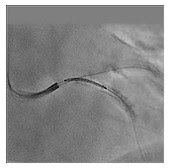

SCORE StentView Realce de stent em tempo real com imagens dinâmicas

O SCORE StentView é a versão mais recente e avançada do StentView, considerada verdadeiramente revolucionária por muitos usuários clínicos, permitindo realçar os stents e ajustar a posição em imagens dinâmicas em tempo real.

A função para especificar a região de interesse (ROI) agora permite que vários marcadores sejam usados para detecção automática, o que contribui para uma maior eficiência de detecção e tempos de exame mais curtos.